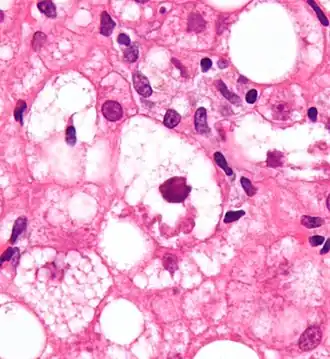

![]() Micrograph showing a Mallory body, a histopathologic finding associated with alcoholic hepatitis. H&E stain. | ||